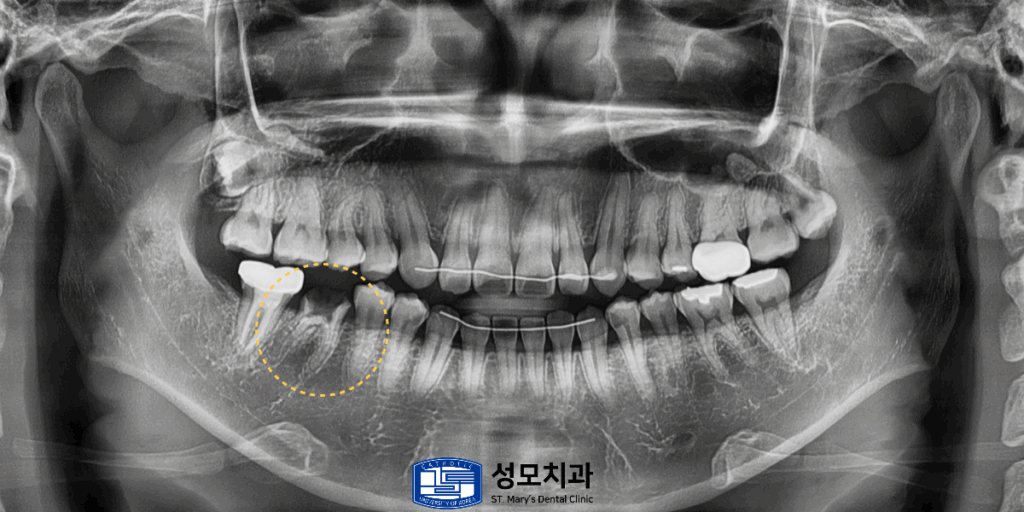

5. 치료 과정을 촬영한 파노라마 사진

x-ray를 촬영해 보면 남아있는 건강한

치아 부분이 매우 적고 이미 신경 입구 부분이

상당히 넓게 개방되어 감염 우려가 높았으므로

재치료가 필요한 상황으로 판단되어

의정부치과, 의정부성모치과에서는

신경치료를 통해 감염된 부위를 제거하고

철저하게 소독한 뒤 내부 공간을

다시 충전하는 과정을 거쳤습니다.